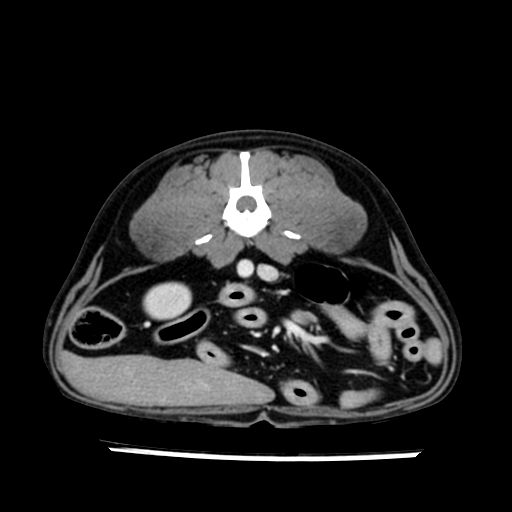

prescritto esame TAC

sequenza immagini limitata al fegato reni e surreni

le immagini ecografiche rispetto alla tac datano circa 7 mesi prima ,le surrenali sono normali nonostante il test acth sia risultato positivo .all’esame TAC dopo diversi mesi risultano aumentate armonicamente nel volume e si individua un forte sospetto di adenoma ipofisario .

sospetto adenoma ipofisario vs. meno probabilmente meningioma della base; intertiziopatia polmonare; lesione espansiva epatica, verosimilmente del lobo laterale sinistro, di sospetta natura neoplastica; lesioni spleniche di natura da definire; iperplasia/ipertrofia delle ghiandole surrenali, bilateralmente; vertebra di transizione del rachide toracico; tenosinovite cronica del muscolo bicipite brachiale di destra.